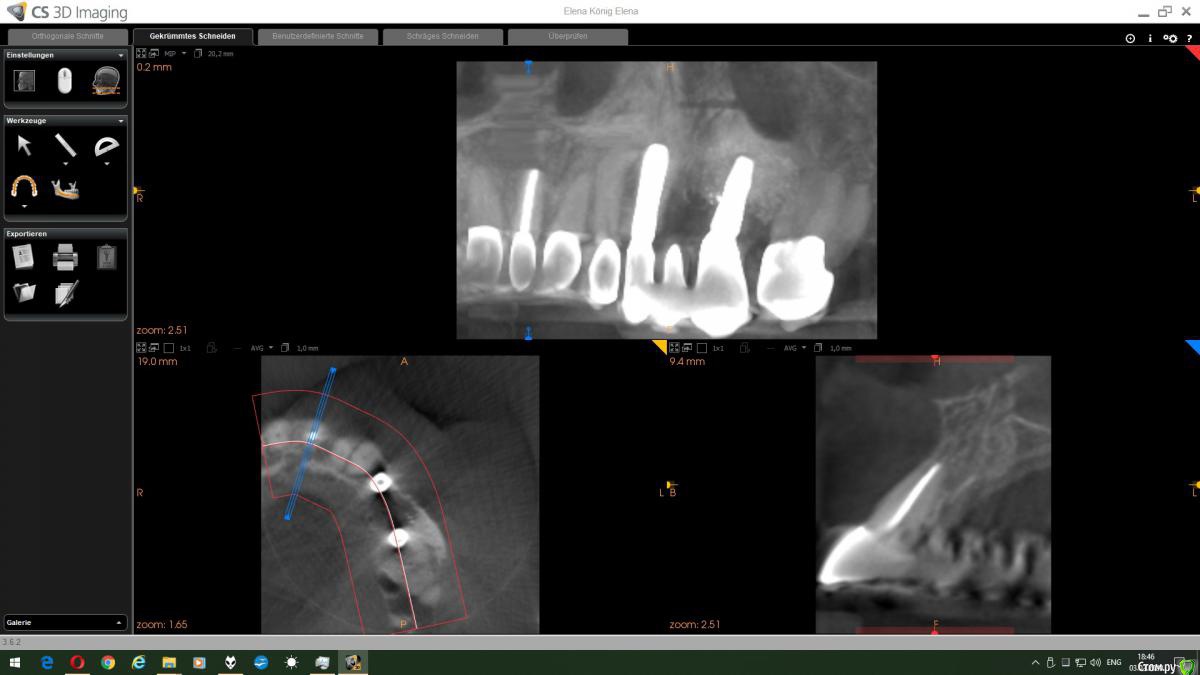

ellenchik Опубликовано 2 февраля, 2020 Автор Поделиться Опубликовано 2 февраля, 2020 Снимок свежий-08.01.2020 Врач прописал пока Амоксиклав на 5 дней. КТ постараюсь на след. неделе сделать. Большое спасибо всем Докторам за ответы!Доброго дня! Антибиотик к сожалению не помог :-( Болит по прежнему. Сделала КТ верхней челюсти. Врач крутил-смотрел. Ничего определенного не сказал-отправил к хирургу. Ну вот к сожалению, не умею я делать срезы с КТ. Могу только ссылку выложить. С удовольствием бы оплатила консультацию по КТ. Если кто-то откликнется в личку , буду очень признательна. Ну очень надо! Помогите плиииззз. https://dropmefiles.com/f60S3 . Или посоветуйте, к кому можно на форуме обратиться Ссылка на комментарий

wladdX Опубликовано 3 февраля, 2020 Поделиться Опубликовано 3 февраля, 2020 А это точно Ваша КТ? Непохоже на то, что на прицельном снимке. Ссылка на комментарий

Bier Опубликовано 3 февраля, 2020 Поделиться Опубликовано 3 февраля, 2020 Безымянный.jpg А это точно Ваша КТ? Непохоже на то, что на прицельном снимке.согласен, что-то не то Ссылка на комментарий

ellenchik Опубликовано 3 февраля, 2020 Автор Поделиться Опубликовано 3 февраля, 2020 Спасибо огромное,что посмотрели ....хмм.., доктор перекинул на мою флешку. Думаю,что моя. Посмотрела на срез в сообщении № 18 от wladdX. Это левая сторона верхней челюсти с имплантами.А проблема и снимок прицельный с правой стороны. Рядом стоящие резец и клык - оба с пролеченными корнями. В этой стороне боль "гуляет" И непонятно , какой зуб дает такую реакцию . Посмотрите еще ,пожалуйста. Ссылка на комментарий

wladdX Опубликовано 5 февраля, 2020 Поделиться Опубликовано 5 февраля, 2020 На данном КЛКТ поместился только зуб 11 (верхний центральный резец справа), а на прицельном зубы 12 и 13 (боковой резец и клык), получается, что зона интереса в исследование не включена.Зуб 23 (клык слева) на КТ вроде бы без особенностей. Ссылка на комментарий

ellenchik Опубликовано 7 февраля, 2020 Автор Поделиться Опубликовано 7 февраля, 2020 Доброго всем дня, дорогие Доктора! Получила от врача КТ всей верхней челюсти. Посмотрите еще раз,пожалуйста. Область 11-12-13 зубов. Надеюсь правильные номера. ( 12-13 депульпированные.) Спасибо большое всем откликнувшимся!https://dropmefiles.com/MtIoI Ссылка на комментарий